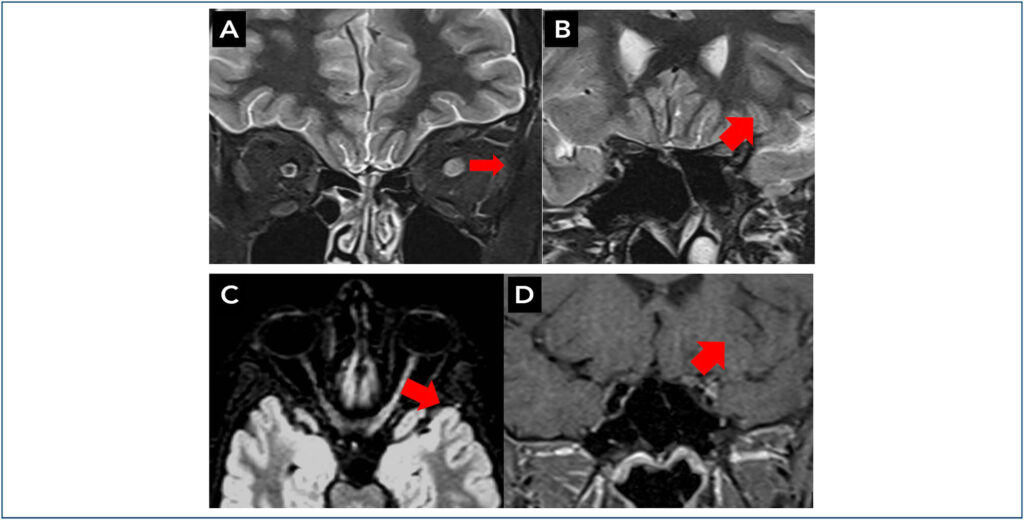

Relato de caso de paciente do sexo masculino de 14 anos que apresentou perda de visão aguda e indolor e inchaço do disco óptico esquerdo. Extensas investigações diagnósticas, incluindo ressonância magnética e testes séricos de anticorpos anti- MOG, foram realizadas. À ressonância magnética, evidenciou-se hipersinal em T2, extenso, na porção anterior do nervo óptico esquerdo, sem envolver quiasma, ou regiões retroquiasmáticas. A estratégia de manejo envolveu metilprednisolona intravenosa seguida de azatioprina, resultando em recuperação completa da visão. Este caso destaca a importância de considerar a neurite óptica associada a anticorpos anti-MOG no diagnóstico diferencial de perda aguda de visão em adolescentes e discute as características clínicas e de imagem que devem levar ao teste de anticorpos anti-MOG.